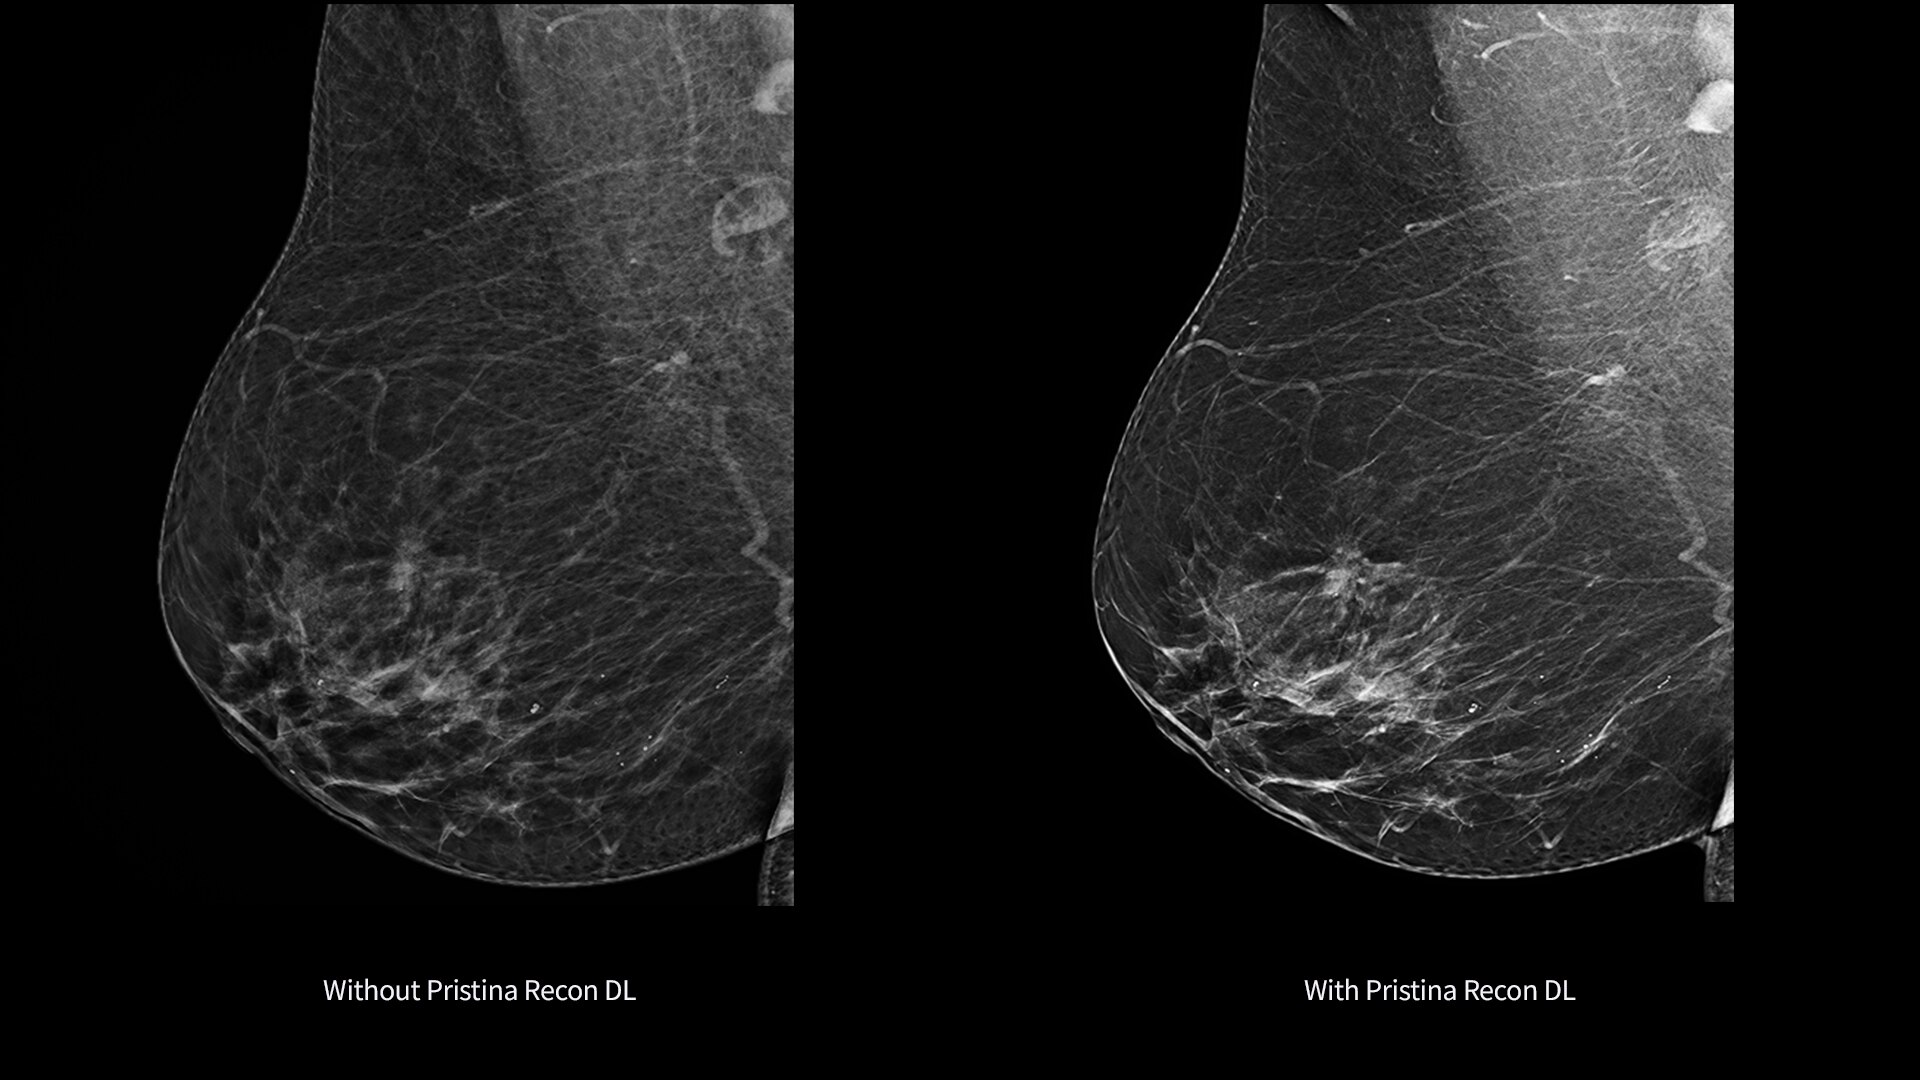

Pristina Recon DL*

The power to detect. The confidence to decide. Introducing groundbreaking technology in mammography image reconstruction, with precision you can see.

Pristina Recon DL gives you the power to detect and confidence to decide.

It pushes the limits of 3D mammography, delivering images with greater purity.

Born from GE HealthCare's pioneering AIR Recon DL in MRI, it represents a paradigm shift in image reconstruction.

Its dual deep learning technology reveals fine details minimizing artifacts and perceived noise1,2, without increasing dose.

Pristina Recon DL reconstructs with scientific precision, transforming breast images into pristine, clear volumes. It uses two deep learning models to improve image quality without changing the acquisition.

The improvement is easy to see, with radiologists surveyed consistently preferring its sharpness1,2 and lesion conspicuity1,2.